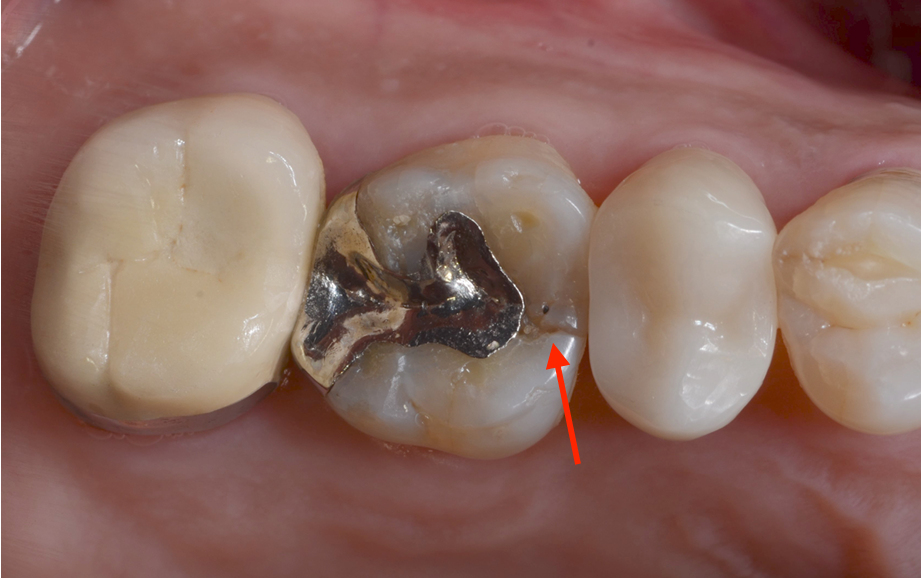

오늘은 오른쪽 위 치아가 불편하셔서

저희 치과를 찾아 주신 환자분의 이야기를 해드릴게요😊

오래 전에 치료 하신

metal inlay(금속으로 메꿔 놓은 치료) 부위

주변으로 꽤 선명하게 금이 간 것도 보이네요

(metal inlay는 한국 치과에서는 자주 하지 않는 치료입니다.

주로 일본에서 장인 정신으로 정말 정교하게 하는 경우는 있지만~)

이런 치아의 진단에는 X-ray가 필수겠죠

“X-ray를 통해 정확히 확인해 봤더니…..”